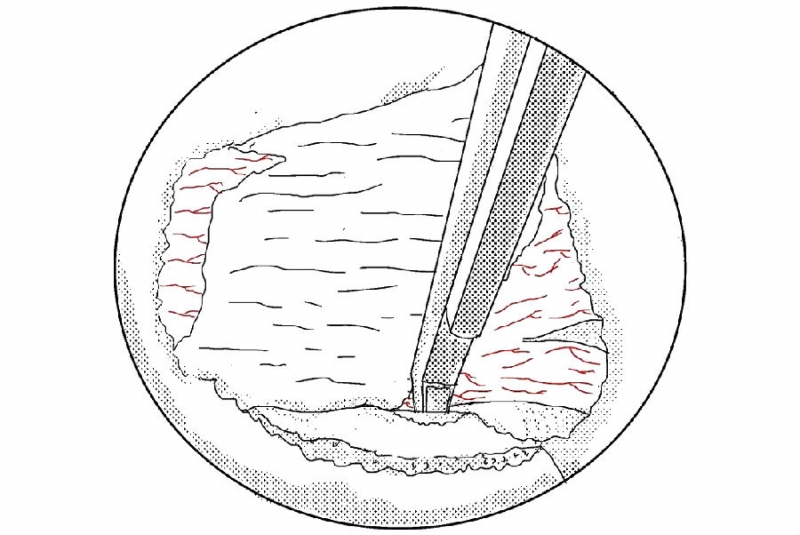

1. 建立通道后的多裂肌三角“地板解剖”;

2. 大刀头清理软组织;

3. 使用4mm金刚砂磨钻将椎板下缘及下关节突内缘磨薄;

4. 使用椎板咬骨钳继续向近端咬除椎板直至黄韧带近端止点;

5. 使用小的射频刀头在止点区域进行止血;